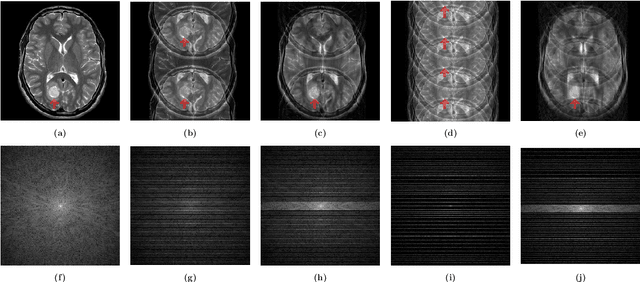

Abstract:This paper presents a deep learning method for faster magnetic resonance imaging (MRI) by reducing k-space data with sub-Nyquist sampling strategies and provides a rationale for why the proposed approach works well. Uniform subsampling is used in the time-consuming phase-encoding direction to capture high-resolution image information, while permitting the image-folding problem dictated by the Poisson summation formula. To deal with the localization uncertainty due to image folding, very few low-frequency k-space data are added. Training the deep learning net involves input and output images that are pairs of Fourier transforms of the subsampled and fully sampled k-space data. Numerous experiments show the remarkable performance of the proposed method; only 29% of k-space data can generate images of high quality as effectively as standard MRI reconstruction with fully sampled data.